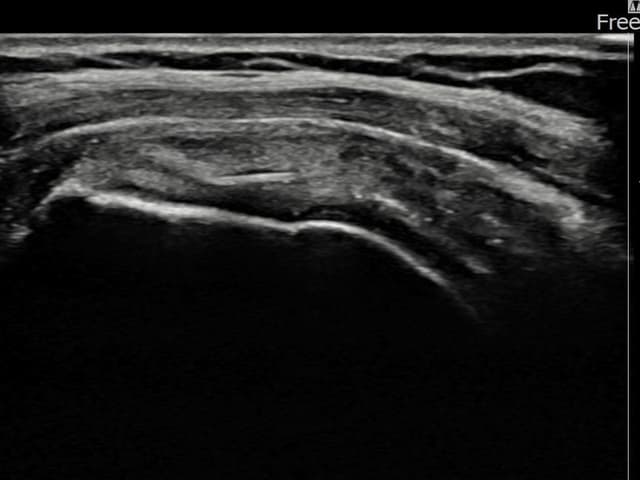

左侧 冈上肌腱 部分撕裂

7mm × 3mm (肌腱厚度约30%缺损)